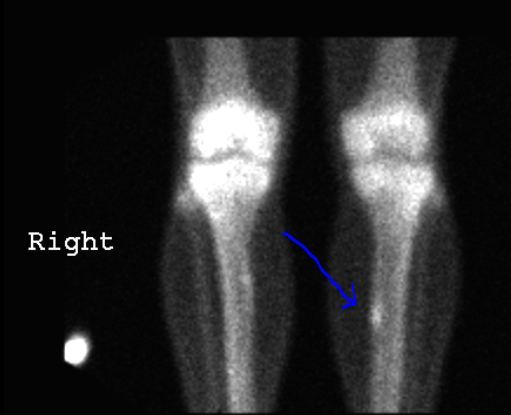

3. Bone Scan

1. How it works

1. A radiotracer that contains a small amount of radioactive material is inserted into a vein

1. The substance travels through the blood to the bones and organs

1. As the substance wears off it leaves traces of radiation

1. The radiation is detected by a camera that slowly scans the body

1. The camera takes pictures of how much the radiotracer collects in the bones

2. What it shows

1. The various bones of the skeleton

2. Uses

1. Find bone cancer or determine if another cancer has spread to the bone

1. Diagnose the cause/location of unexplained bone pain

1. Diagnose broken bones not clearly seen on an x-ray

1. Find damage to bones

2. Bone Scan showing a stress fracture on the right leg